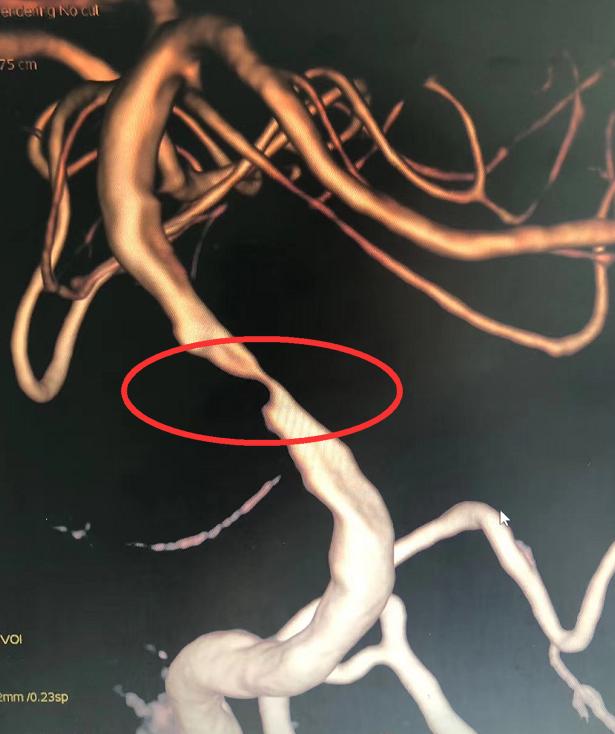

脑病二科主任田立主任医师根据郑大叔病史、查体,结合核磁检查,捕捉到了元凶:基底动脉重度狭窄,不及时处理可能再也无法恢复。

于是请脑病一科主任贾玉勤会诊,贾玉勤主任医师仔细查看患者后建议马上进行脑血管造影并实施“全麻下基底动脉支架成型术”,控制梗塞进展,挽救患者生命。

脑病一科主任贾玉勤主任医师说,与其他颅内动脉狭窄不一样的是,基底动脉直接供血脑干,是生命中枢,即使微小的损伤也可带来难以承受的后果,但若狭窄部位自发闭塞或者手术意外只会令结果更加严重,更为不幸的是郑大叔为基底动脉重度狭窄,狭窄部位有其他小血管分支开口,手术过程稍有不慎就可造成这些分支血管开口闭塞,因此手术难度极大。

脑病一科主任贾玉勤主任医师带领副主任邹云涛等团队成员在介入导管室医护人员及麻醉医师的精心配合下顺利完成手术,采用全身麻醉,术中成功于基底动脉狭窄段置入一枚4*20mm支架,同时保持分支血管的通畅,术后影像效果完美。